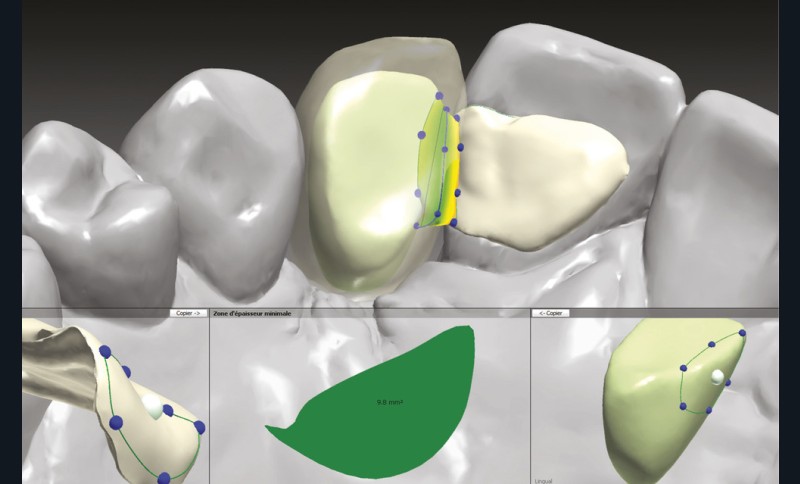

Une fois les modèles virtuels créés, l’armature du bridge est modélisée par Conception Assistée par Ordinateur sur le logiciel Trios Design Studio (3Shape) (fig. 10). La surface de connexion mesurée est de 9,8 mm2 (fig. 11) et celle de collage de 40,56 mm2, respectant ainsi les recommandations de la littérature [24].

Grâce à ses performances mécaniques, une infrastructure en zircone nécessite des surfaces de connexion et des épaisseurs de matériau plus faible que la vitrocéramique renforcée au disilicate de lithium. Néanmoins, cette dernière aura un meilleur potentiel d’adhésion à la dent support. Le risque d’échec principal des armatures en zircone qui en découle est le décollement de l’ailette, alors que dans le cas de l’utilisation de la vitrocéramique, il s’agira en majorité d’une fracture [33].

La zircone permet ainsi de réduire de façon importante le risque de fracture entre l’ailette et le pontique, ce qui augmente les possibilités de réintervention (réassemblage sur le pilier). De plus, l’obtention d’une embrasure plus harmonieuse et naturelle est facilitée. La section entre l’intermédiaire et l’ailette des cantilevers a été décrite de façon empirique, en se fondant sur une étude des surfaces de connexion minimales pour les bridges conventionnels [34]. Avec le mouvement différentiel des dents supports et les forces de cisaillement qui s’appliquent dans un bridge conventionnel, il a été admis qu’une surface au minimum identique serait suffisante pour un bridge collé à une ailette [34].

Aujourd’hui, la conception numérique offre un outil performant pour calculer efficacement la taille de la connexion, la surface de collage et les rayons de courbures. Cette gestion numérique est facilitatrice d’un contrôle optimal de ces paramètres, lors de la conception de l’élément prothétique.